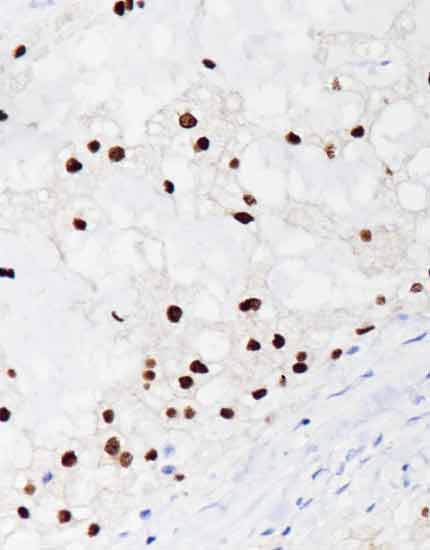

产品名称:Brachyury

产品编号:RMA-1062

阳性部位:细胞核/细胞质

图片描述:

脊索瘤,Brachyury染色,细胞核阳性